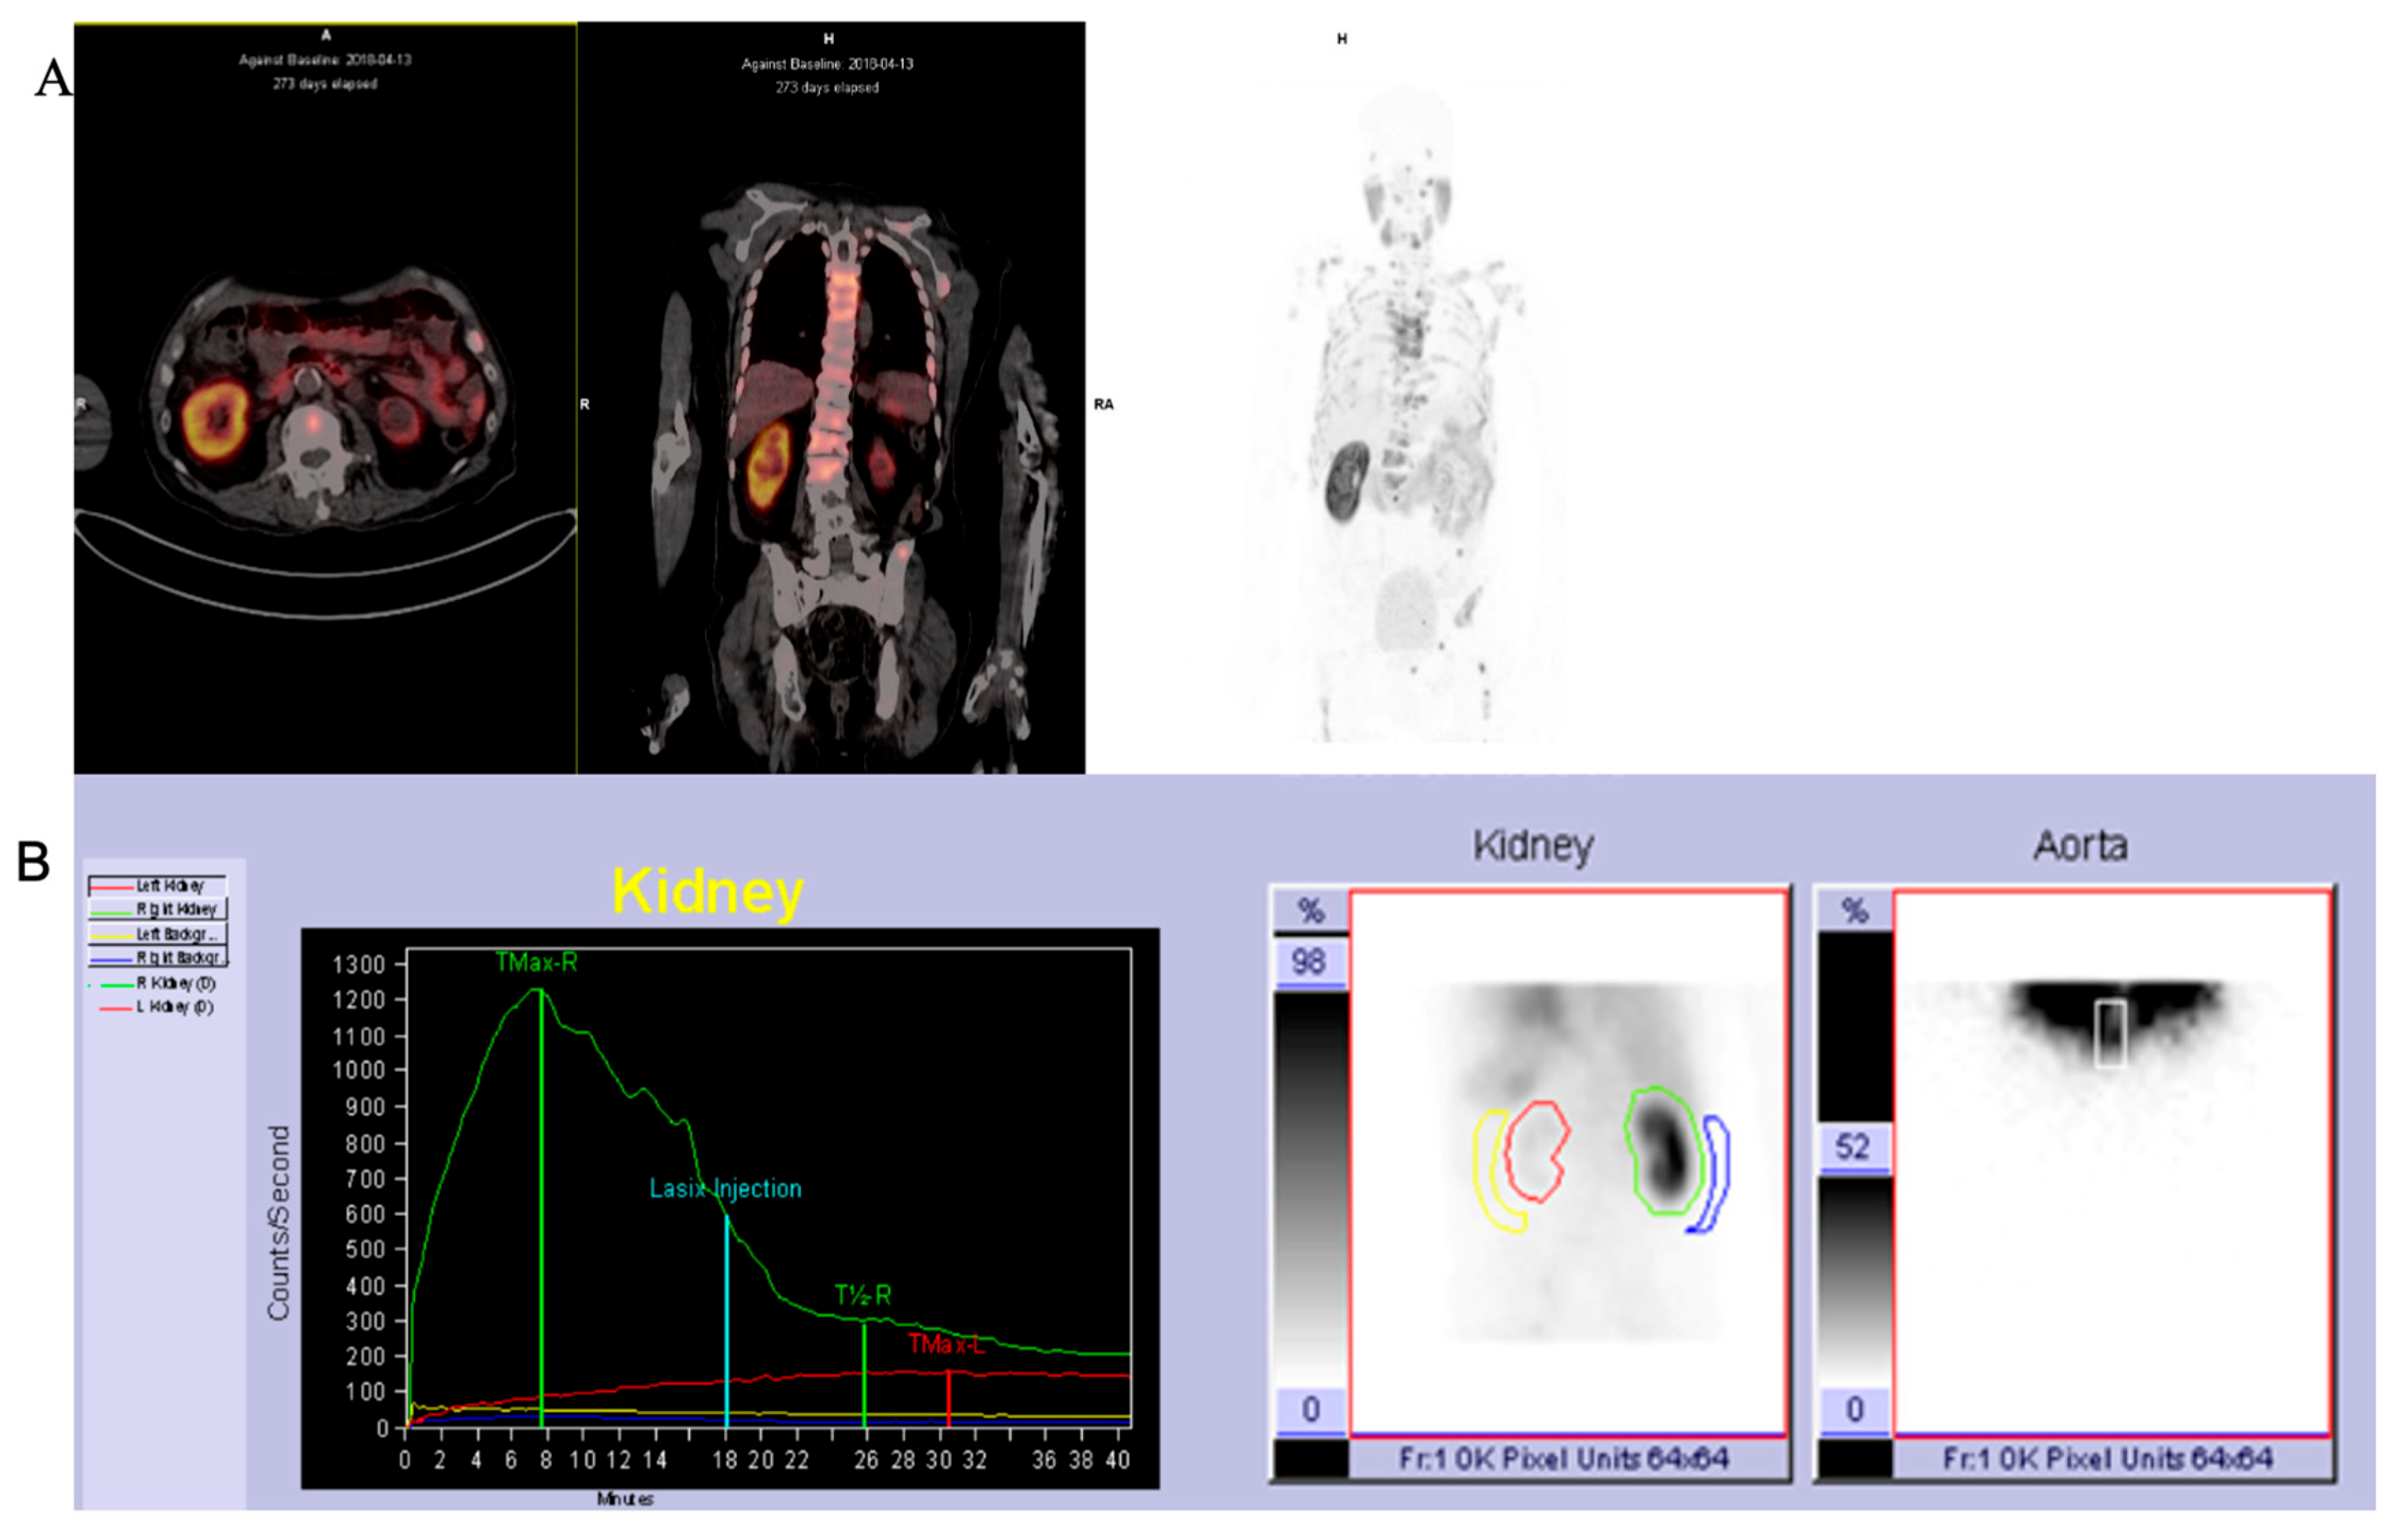

2.1.1. 68Ga-PSMA PET/CT

2.1.2. 68Ga-PSMA PET/CT Image Analysis

2.1.3. 99mTc-MAG3 Renal Scintigraphy

3.2. Comparison of SRF for 99mTc-MAG3 and PSMA

3.3. Comparison of Morphological Abnormalities